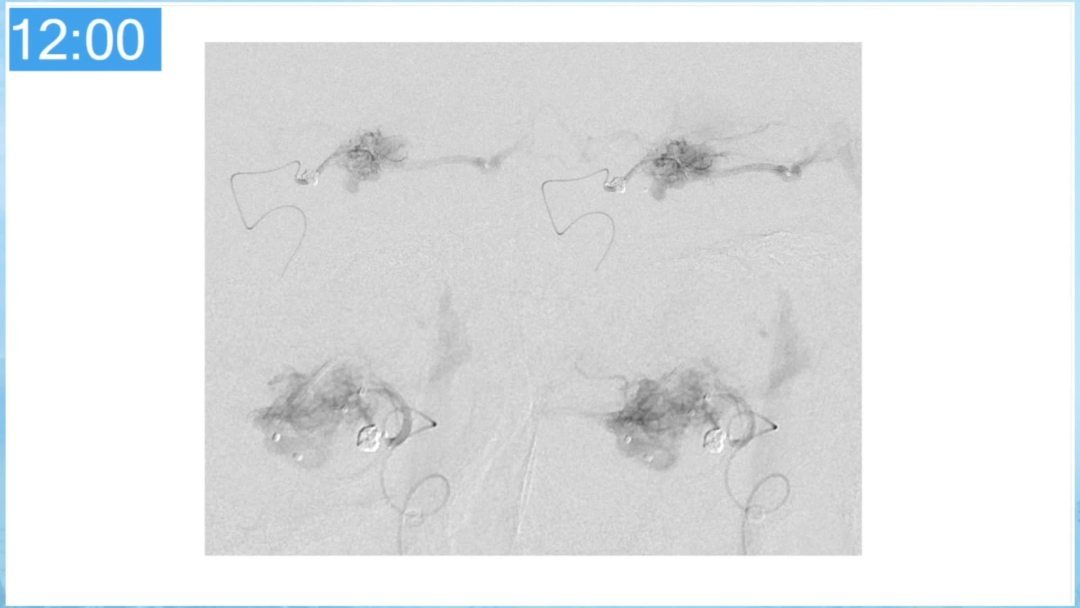

合理的复合平台下的综合治疗,针对每一个病变对应不同方法安全性分析,不预设、不排斥,每种技术发挥到最佳,互相保障。

本期为大家特别分享:空军军医大学唐都医院邓剑平教授的精彩会议内容《颅内动静脉畸形的复合手术治疗》,欢迎大家阅读和分享!